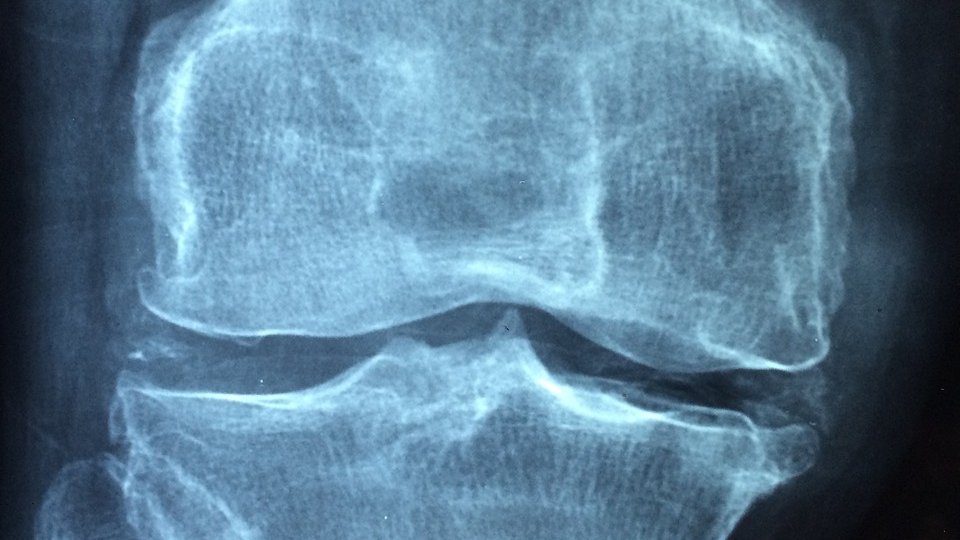

Reumatism: pași mici pentru ameliorarea artritei și osteoartritei

Cartilajul uzat și inflamația provoacă rigiditate și durere la nivelul articulațiilor. Osteoartrita și artrita sunt forme foarte frecvente de reumatism. Medicamentele antiinflamatoare oferă o ameliorare eficientă, dar anumite gesturi și alte sfaturi vă pot ajuta, de asemenea, să vă calmați durerile reumatice. Încercați-le fără niciun risc de efecte secundare.

Supraponderalitatea favorizează și agravează osteoartrita, în special la nivelul genunchilor și șoldurilor, deoarece aceste zone trebuie să suporte mai multă presiune.